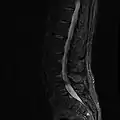

MRI lumbar spine with degeneration (sagittal T2 FRFSE)